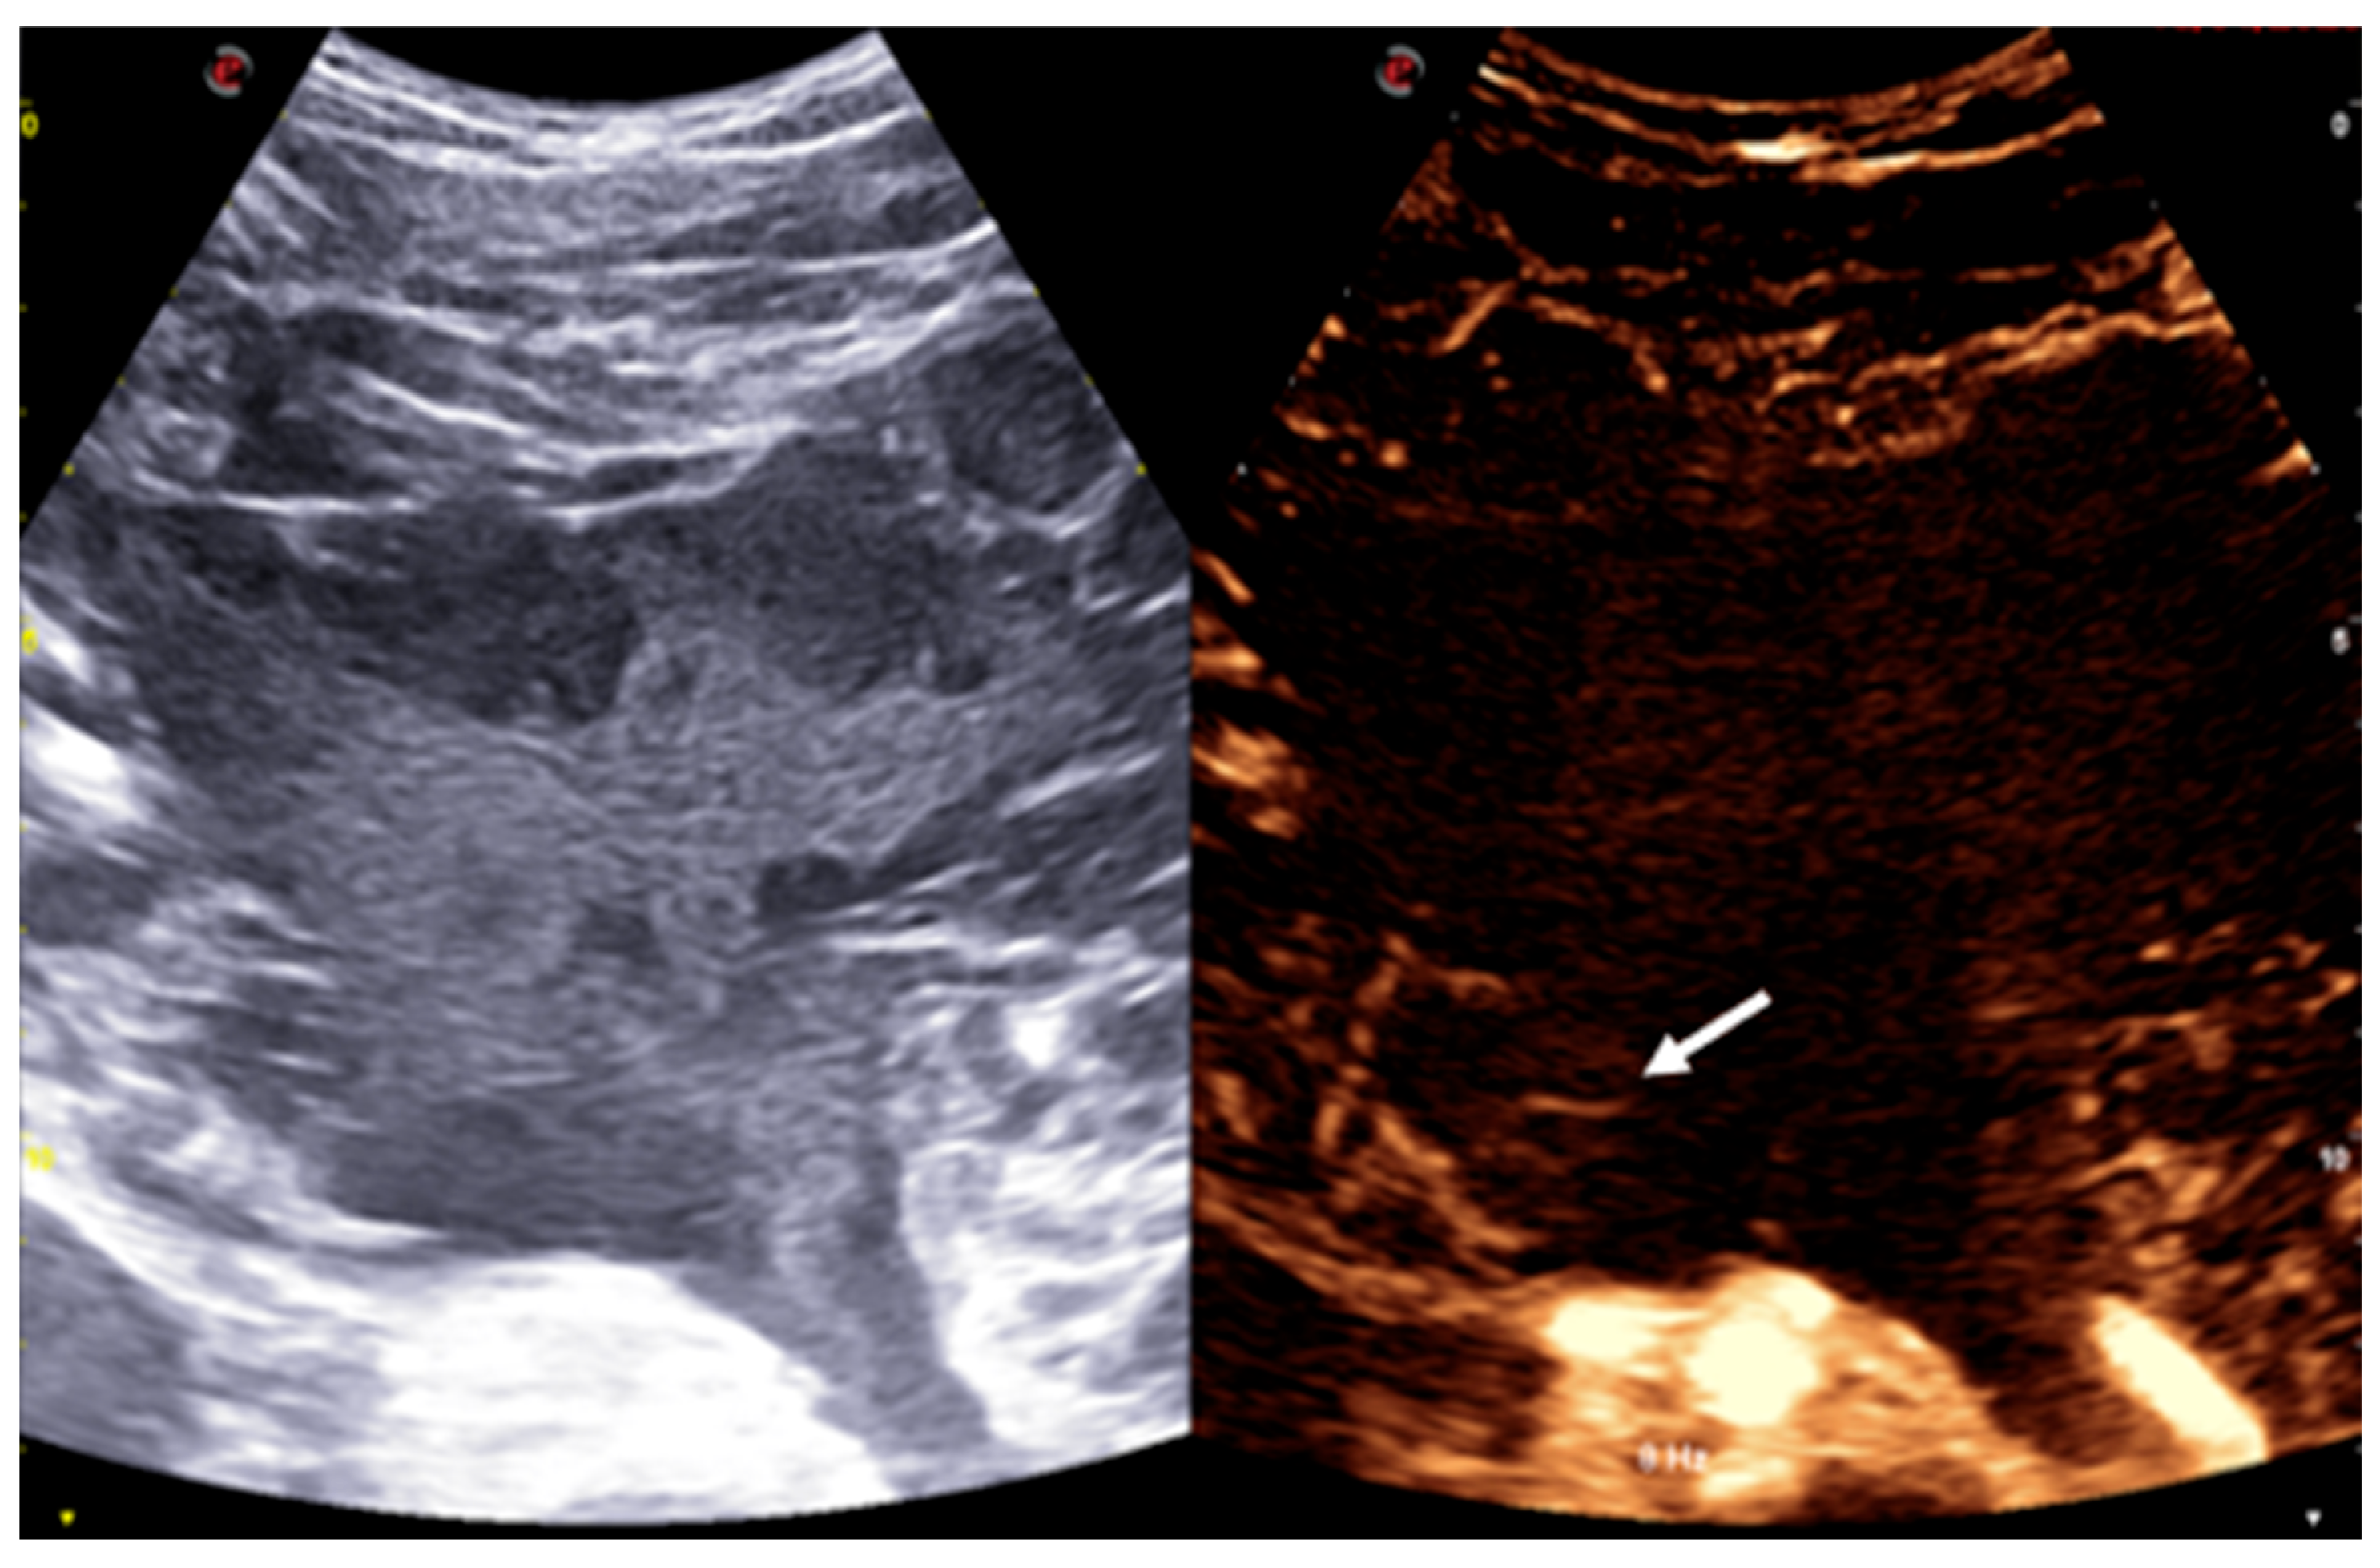

Figure 3. CEUS shows a multicystic lesion composed of individual cysts surrounded by a debris-filled matrix that does not enhance after contrast administration, except for some of the more peripheral septa, which demonstrate mild contrast enhancement (arrow).

Given the imaging characteristics and the broad differential diagnosis, including both benign and malignant entities, an ultrasound-guided biopsy was performed under contrast-enhanced ultrasound (CEUS) guidance. The mass itself showed no contrast uptake, except for some peripheral septa, which exhibited mild contrast enhancement (Figure 3).